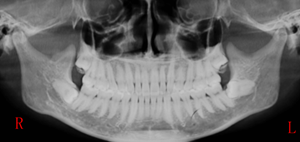

是不是很驚喜,是不是很easy,這個(gè)姿勢(shì)點(diǎn)你get到了嗎?

來源:趙吉宏教授